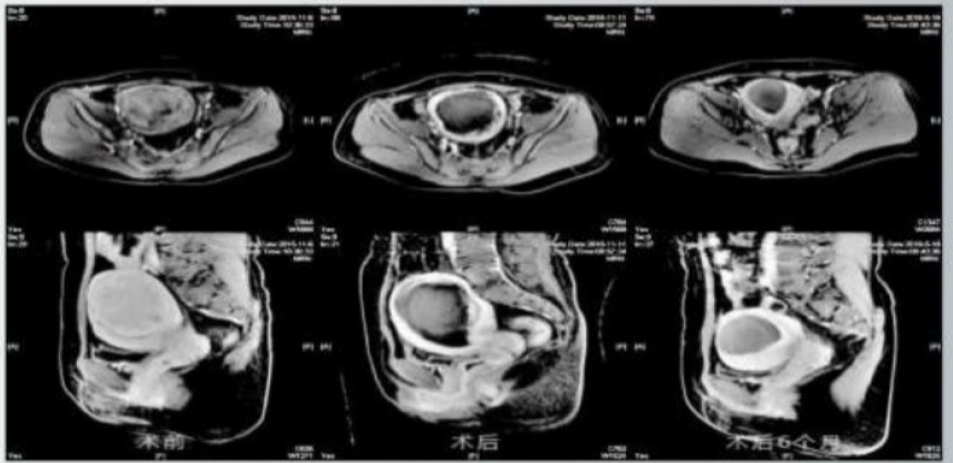

Ablation with coagulative necrosis was achieved in 100% of treated lesions. At 6 months, 73% of tumors show ≥50% volume reduction; supplementary sessions deliver ≥95% reduction in remaining cases.